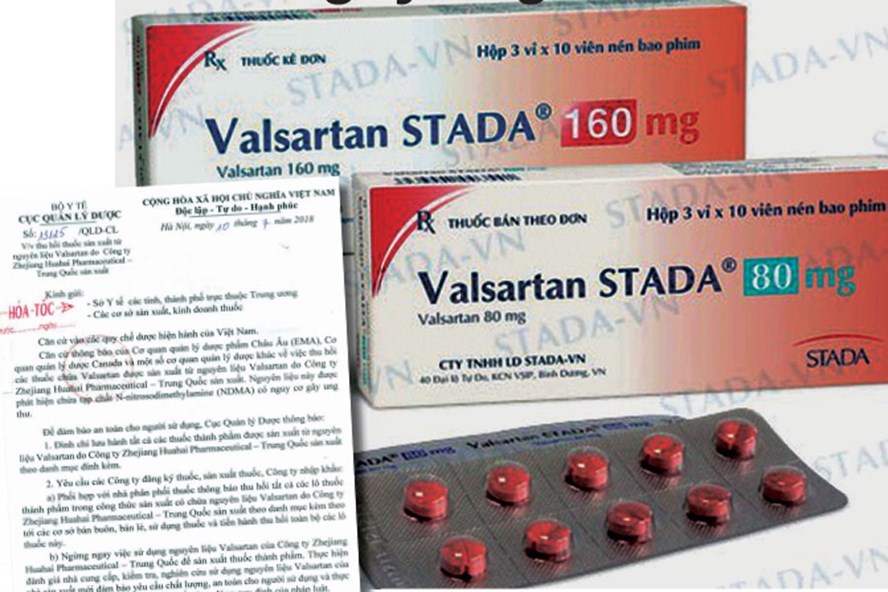

Cục Quản lý dược - Bộ Y tế vừa có công văn khẩn gửi Sở Y tế các tỉnh, thành phố trực thuộc Trung ương; các cơ sở sản xuất, kinh doanh thuốc về việc thu hồi thuốc sản xuất từ nguyên liệu Valsartan do Công ty Zhejiang Huahai Pharmaceutical - Trung Quốc sản xuất